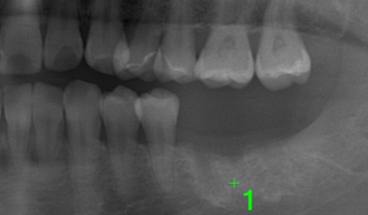

主訴:奥歯で噛めるようになりたい

Before

症例情報

| 通院時の年齢 | 45歳 |

|---|---|

| 性別 | 女性 |

| 通院回数 | 6回程度 期間3ヶ月 |

| 通院目的 | 入れ歯を入れたくない |

| 処置内容 | インプラントを入れる治療 |

| 費用 | 85万(歯周病治療は保険治療) |

| デメリット・注意点 | 歯周病にかかっている患者さんは治療からインプラント治療に至るまでに1年近くかかる場合があります 治療後はれる可能性があります 虫歯の治療が並行して必要な場合があります |

| 備考 | 入れ歯による保険のかみ合わせの修復は引っ掛ける歯の寿命を短縮させ、せっかく治療したのにその引っかけの歯の歯茎がすぐに下がって虫歯になってしまう可能性や抜歯になってしまう可能性があります セラミックを使うインプラント上部の歯を使用することでインプラントの歯周病のリスクを下げることが出来ます |